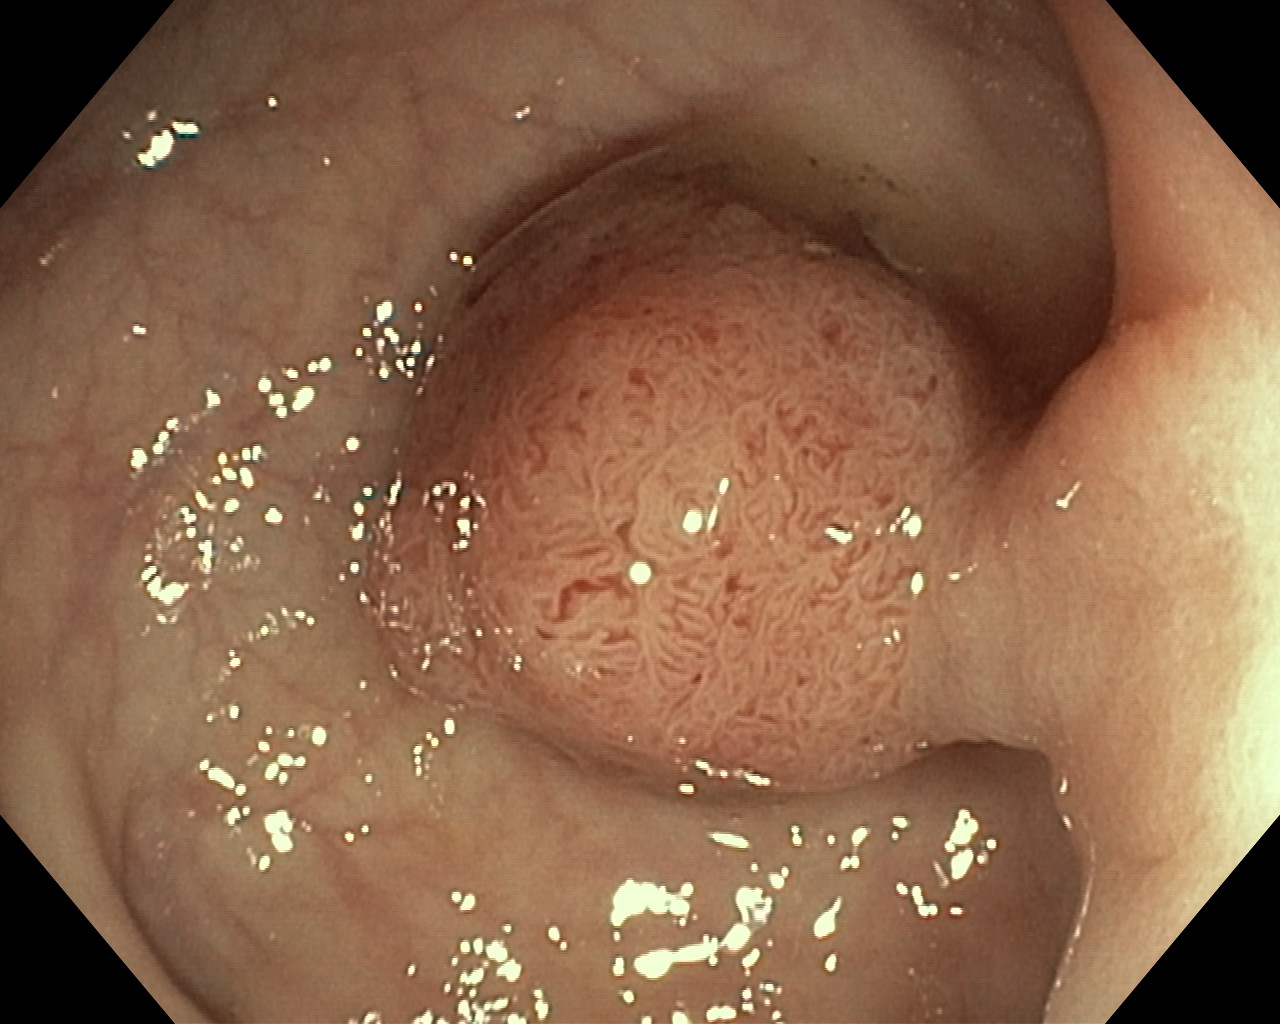

Polipy